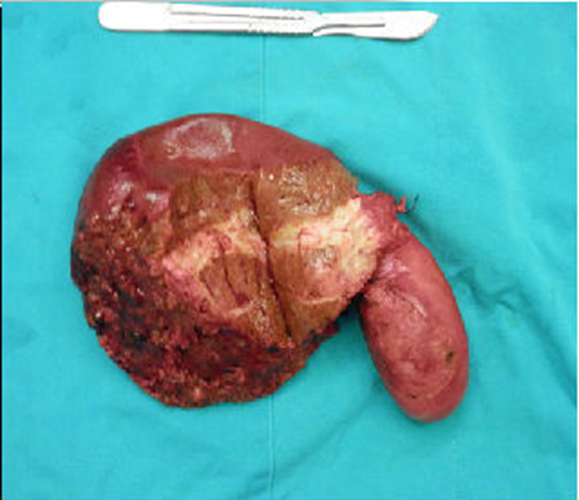

肝內膽管癌